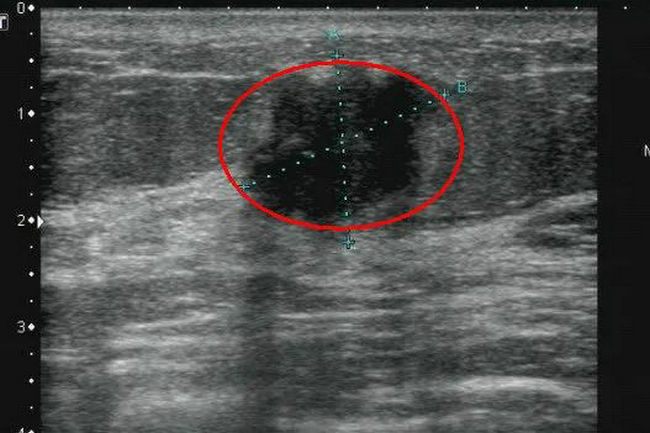

▲ 乳腺癌

超声报告单中,对于各类结节都会有详细描述,其中椭圆形或圆形、边界清晰、未见血流信号的以良性居多。而纵向生长、形态不规则、边缘不清楚、内有点状及簇状钙化、血流信号丰富的,则要警惕恶性病变的可能。